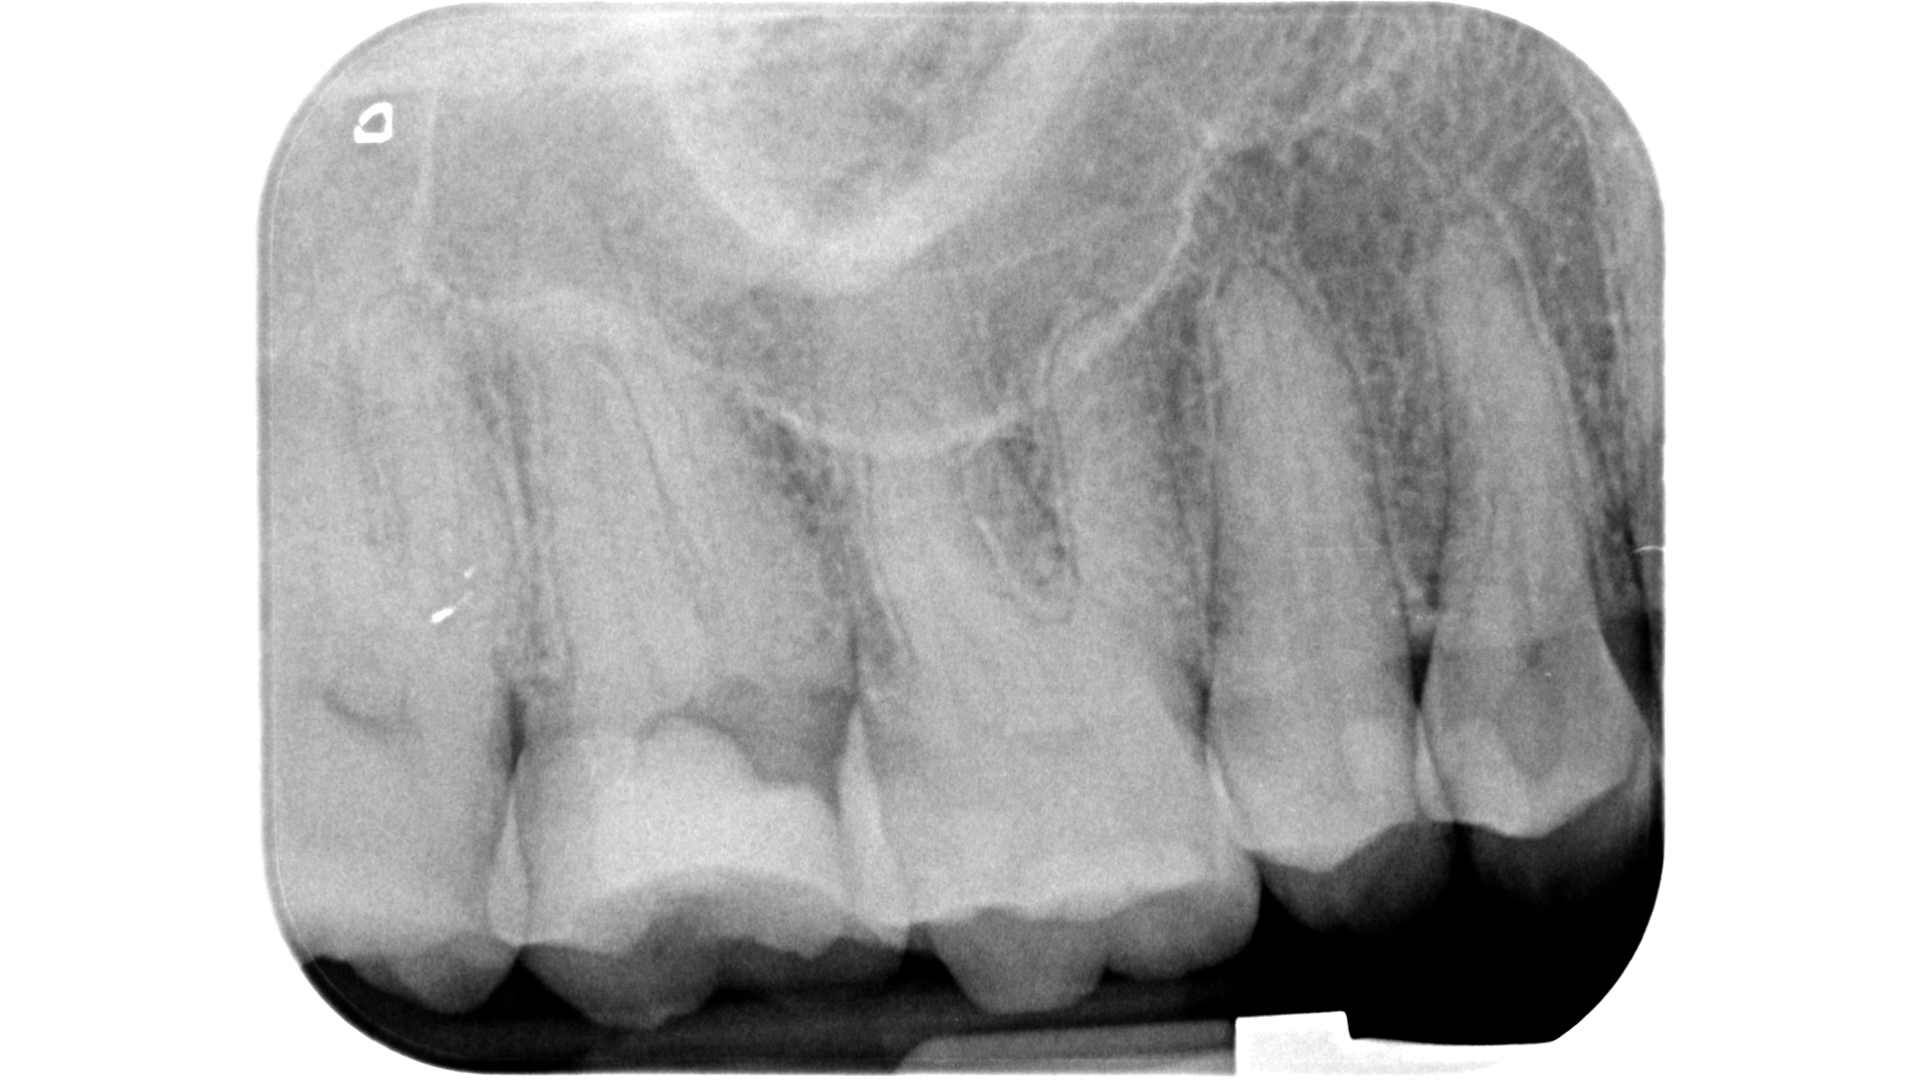

Fig. 27: Pre-op radiograph of a maxillary molar. Note the evident contraction of the pulp chamber and the root canal system.

Fig. 28: Identification of white dots of dentinal powder accumulated in correspondence with the canal orifices during the selective removal action with the EndoTracer bur.

Fig. 29: Identification of white dots of dentinal powder accumulated in correspondence with the canal orifices during the selective removal action with the EndoTracer bur.

This selective grinding of dentine can deposit white powder on the orifice in a very short time. Therefore, if the first steps have not made it possible to locate the canal, it is advisable to alternate between irrigation with sodium hypochlorite and drying and then start again with a new excavation cycle (Figs. 27–33). This stop-and-go approach will help avoid any mistakes.